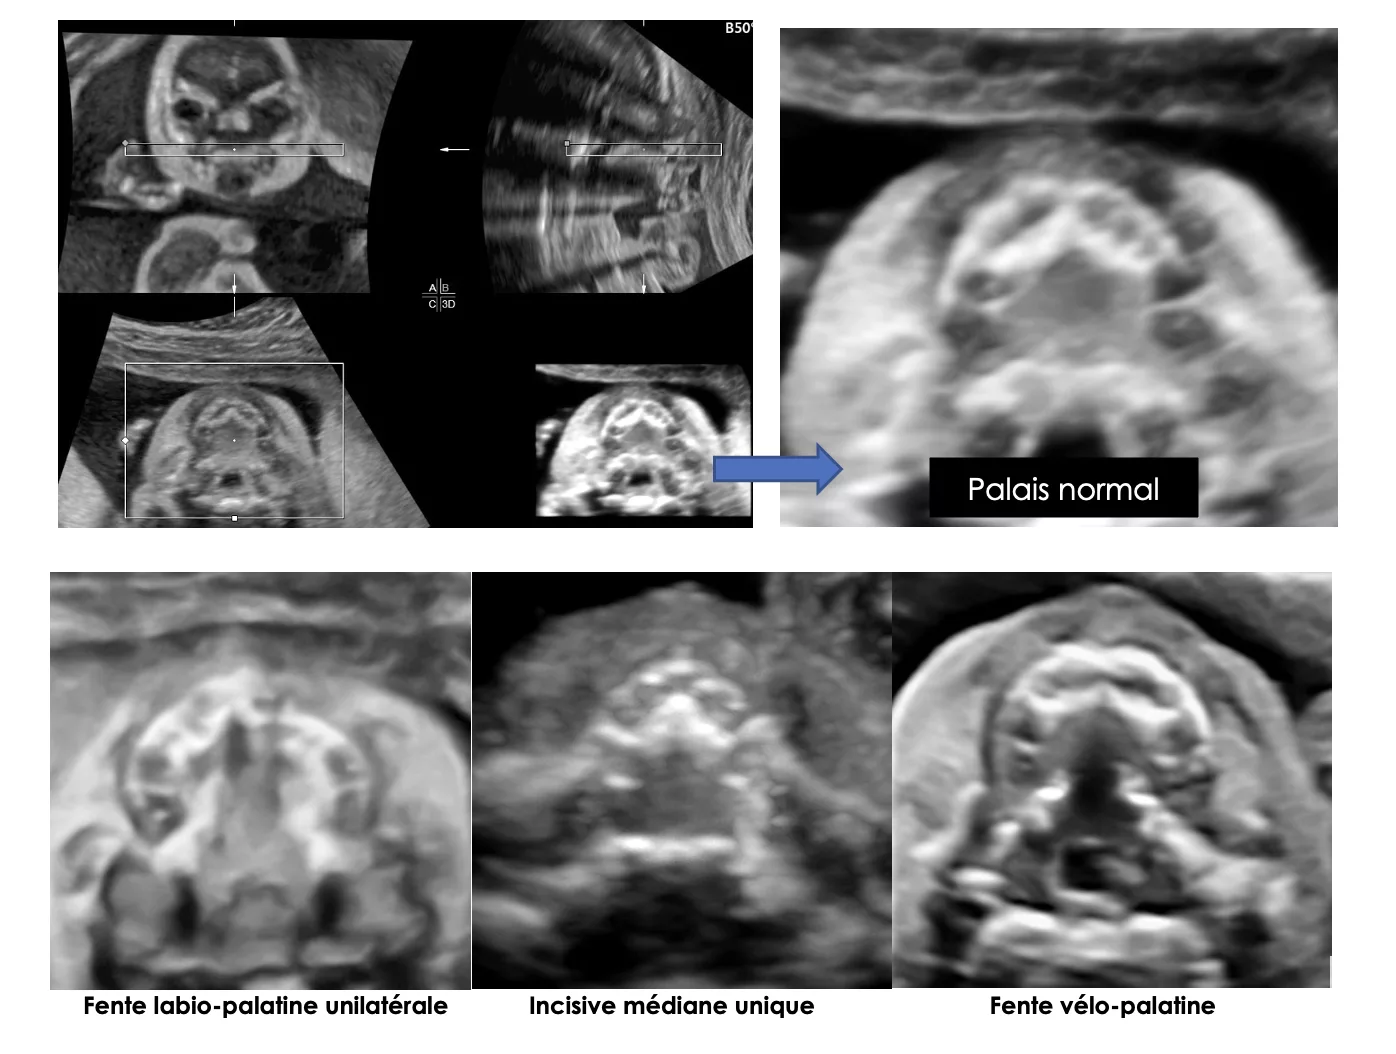

- Prenatal ultrasound diagnosis of cleft palate without cleft lip, the new ultrasound semiology. Faure JM, Mousty E, Bigorre M, Wells C, Boulot P, Captier G, Fuchs F. Prenat Diagn. 2020 Jul 16.

- A score-based method for quality control of fetal hard palate assessment during routine second-trimester ultrasound examination. Fuchs F, Burlat J, Grosjean F, Rayssiguier R, Captier G, Faure JM, Dumont C. Acta Obstet Gynecol Scand. 2018 Nov;97(11):1300-1308.

- The 2D axial transverse views of the fetal face: A new technique to visualize the fetal hard palate: methodology description and feasibility. Fuchs F, Grosjean F, Captier G, Faure JM. Prenat Diagn. 2017 Dec;37(13):1353-1359.

- Prenatal diagnosis of an isolated incomplete V-shaped cleft palate using a new three-dimensional ultrasound technique investigation. Faure JM, Bäumler M, Bigorre M, Captier G, Boulot P. Surg Radiol Anat. 2007 Dec;29(8):695-8. Epub 2007 Nov 13.

- Sonographic assessment of normal fetal palate using three-dimensional imaging: a new technique. Faure JM, Captier G, Bäumler M, Boulot P. Ultrasound Obstet Gynecol. 2007 Feb;29(2):159-65.